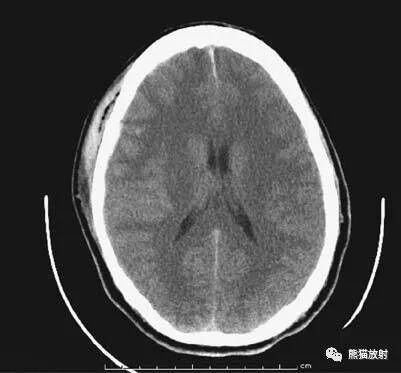

正常解剖

- 鞍上池:在垂体窝上方,位于两侧颅中窝之间,前界为颞叶直回,侧方位颞叶海马,呈五角星形或六角星形。其前角连于纵裂池,两外侧角连于外侧裂池,两后外侧角延续于环池,第六个角位于后缘中间,是角间池。鞍上池边缘为大脑动脉环,池内前部常可见“v”字型视交叉。